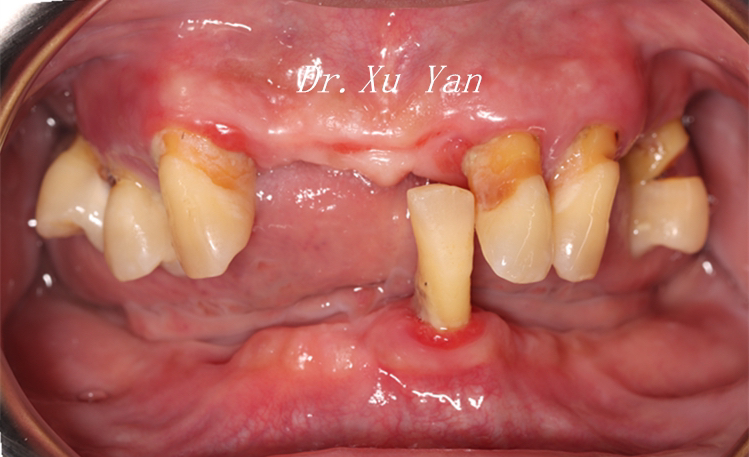

经徐医生检查张叔全口牙槽嵴呈重度吸收,形态呈刃状,存在明显的凹陷性骨吸收。活动义齿基牙颌面磨损严重,基托边缘与组织面不密合,固位及稳定性差。

术前口内咬合照

术前口内下颌照